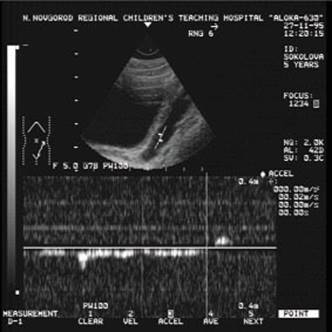

Доплерограма

На малюнку помітно зниження функції нирок виявляється ненасичений інтраренального малюнка, зниження по часу або мінімальної швидкості кровотоку. Всі ці критерії характеризуються патологією і потребують оперативного втручання.

Сканування лівого сечівника через сечовий міхур. На доплерограмах чітко видно криву ретроградногопотіку сечі. Швидкість потіку 0,52m/s, Час 1,16s)

Сканування лівого сечівника через сечовий міхур. На доплерограмах чітко видно криву ретроградногопотіку сечі. Швидкість потіку 0,22m/s, Час 2,38s)

На доплерограмі сечоводів СМР 2,3 і4 ступені спостерігається: делятація сечівника в нижніх і верхніх відділах при середньому або максимальному наповнені сечового міхура, циклічні зиіни діаметра сечівника в нижніх і верхніх відділах: доплерографічна регістрація зворотнього току сечі в сечоводі:стабільне розширення миски: зменшення розмірів нирки.